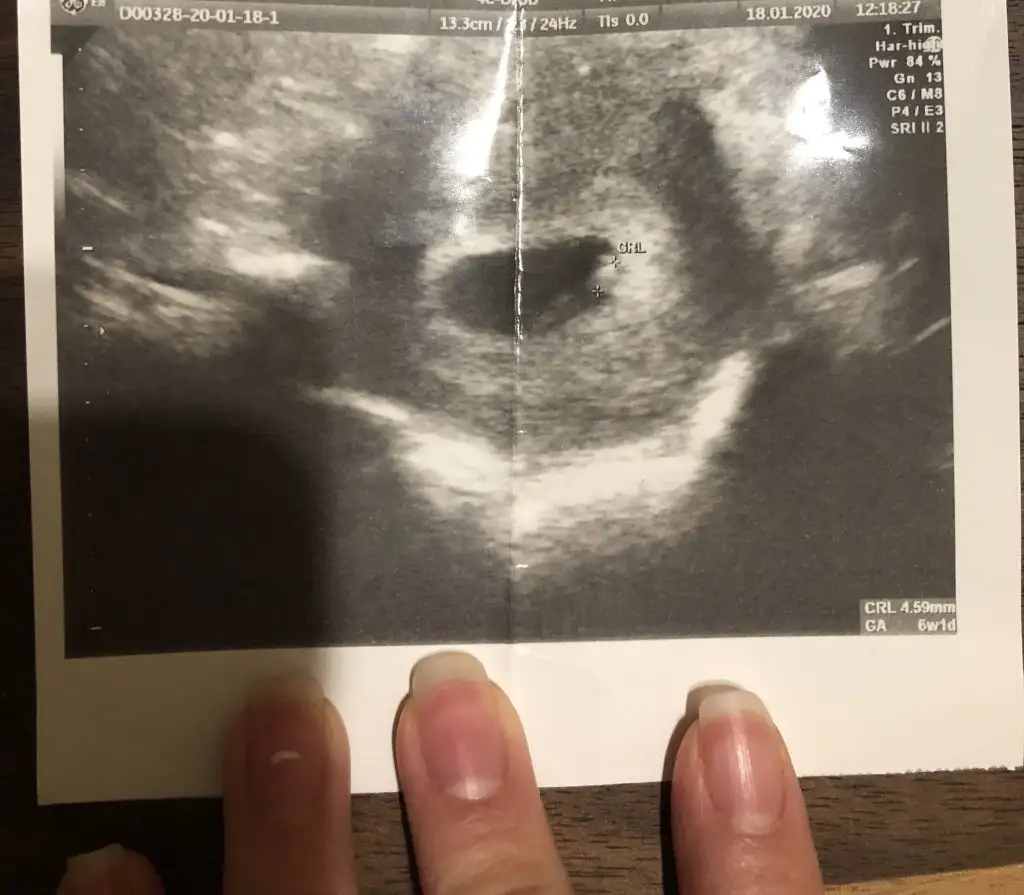

Kızlar merhaba 6+1de bebeği gördük ve kalp atışını duyduk Şükürler olsun ki, ancak benim hesaplamama göre sat a göre 5 gün eksik gözüküyor, yumurtlama dönemimde hiç ilişki olmamıştı geç döllenme olduğu için mi geride gözüküyor acaba, böyle bir durum yaşayan var mı?

• 28CD32A9-09F2-421C-A4A2-6CF8EEB3BDA4.webp

37,4 KB · Görüntüleme: 64